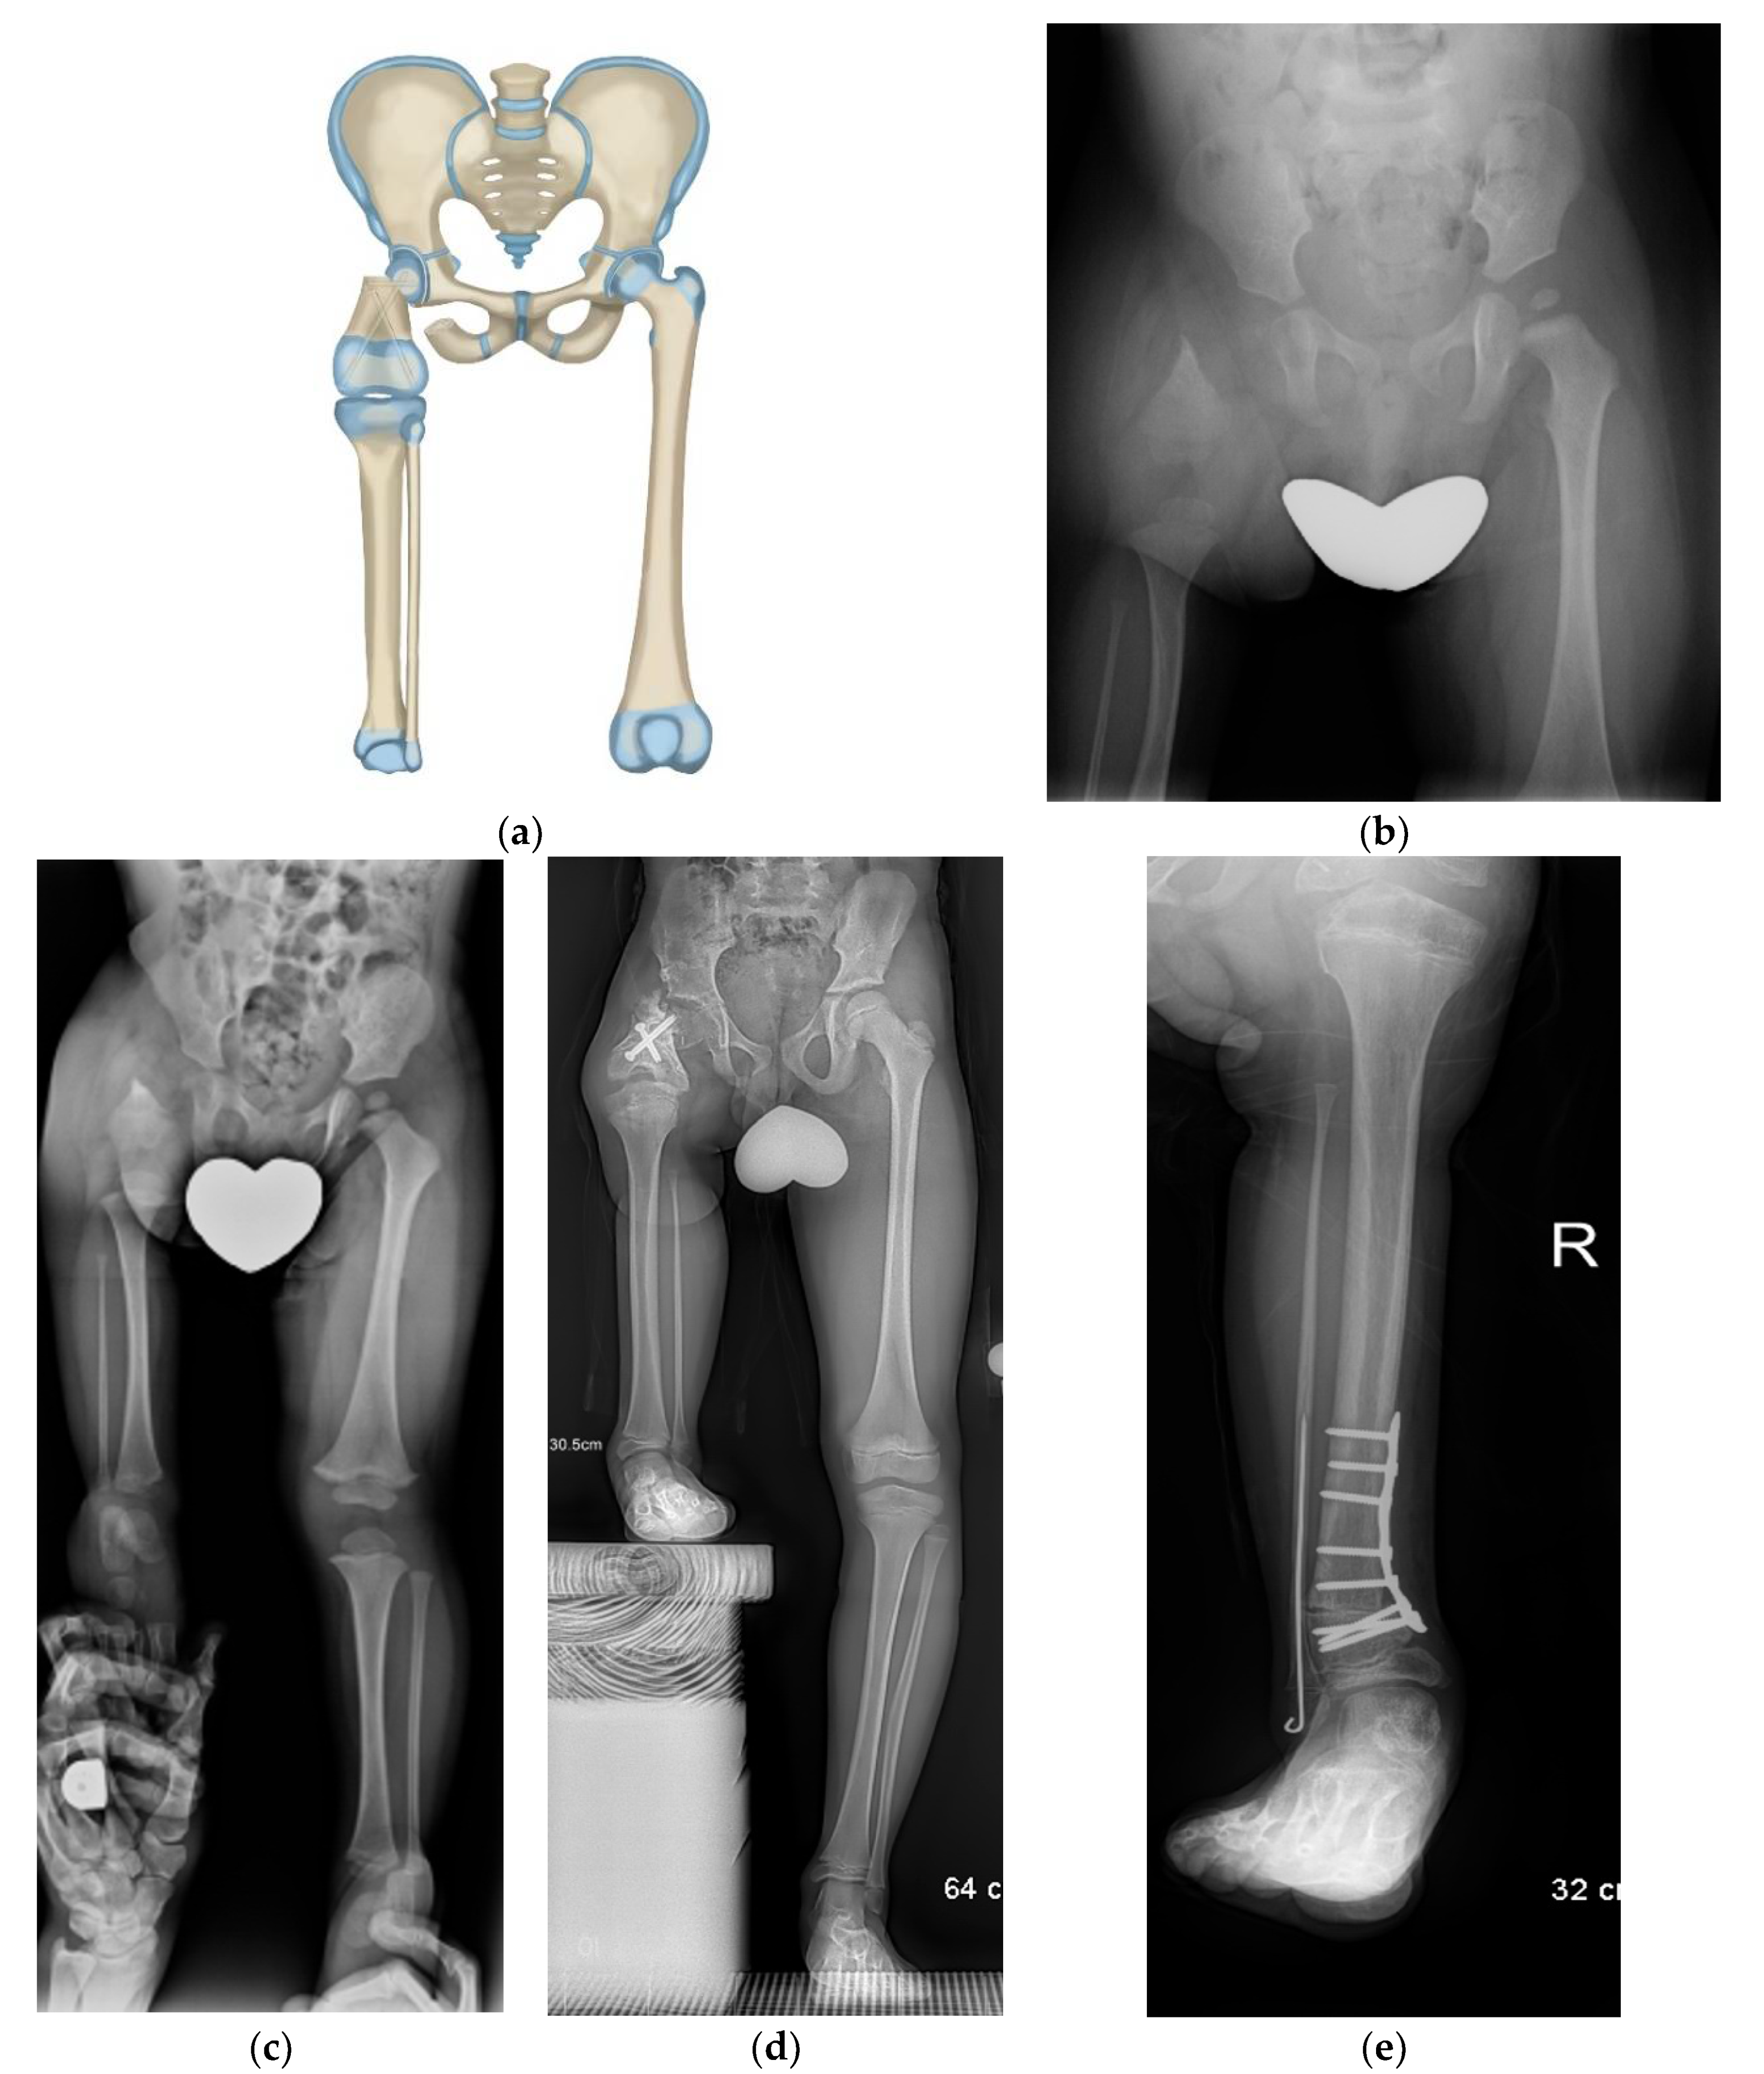

In a subset of Paley type 3a or 3b or in Paley type 2a CFD patients, there is a mobile femoral head in the acetabulum. This can be determined before surgery using MRI. In these cases, the distal femoral remnant can be fused directly to the femoral head (Paley rotationplasty) (Figure 4a–e). Paley started using this method for selective cases since 2012. This creates a more 3-dimensional hip motion flexing and extending through the rotated knee joint and abducting-adducting and axially rotating through the femuro-acetabular joint.

Figure 4.

(a) Paley rotationplasty illustration. (b) AP pelvis of 2-year-old boy with CFD Paley type 3a. (c) Standing radiographs in same boy before surgery showing ankle is at level of opposite knee. (d) Since the femoral head was mobile a Paley rotationplasty was performed. Standing long radiograph in same boy, 8 years after Paley rotationplasty. (e) To improve his prosthetic fitting he had a varus derotation surpramalleolar osteotomy performed 8 years after the original rotationplasty. Clinically he is very sports active and has excellent gait and function.

Neither the Brown, Paley–Brown, nor Paley types of RP are indicated if there is complete absence or ankylosis of the knee joint with an absent femur (Paley type 3c). Winkelmann articulated the lateral plateau of the tibia with the acetabulum when performing rotationplasty for total femur resection in sarcoma patients. Paley modified the Winkelman RP in 2014 to treat CFD type 3c (Figure 5a–g). He used the same circumferential incision as in the Paley–Brown without the second circumferential incision used in the Winkelmann to shorten the thigh since the limb is already shortened, adding a suture tethering system to maintain the tibia in the hip joint (e.g., syndesmotic suture washer device or suture anchor device). With this method the lateral side of the tibial plateau or dysplastic remnant of distal femur articulate with the acetabulum after first enucleating the femoral head (Paley–Winkelmann rotationplasty).

Figure 5.

(a) Illustration of CFD Paley type 3c. There is an ankylosed knee with a small distal femoral remnant. (b) Illustration showing the femoral head is enucleated to make room for the femoral condyle or tibial plateau in the acetabulum. (c) Paley–Winkelmann rotationplasty illustration, inserting the femoral condyle remnant into the acetabulum secured with a hip tethering suture. (d) AP pelvis radiograph of a 12-year-old girl with CFD Paley type 3c. (e) Standing long radiograph of same girl showing the ankle is at the level of the opposite knee. (f) AP pelvis radiograph of same girl after Paley–Winkelmann rotationplasty with femoral condyle in the acetabulum. The tethering suture anchor is seen. (g) Standing radiograph of same girl 5 years after Paley–Winkelmann rotationplasty. She has excellent function of the new hip joint and can walk and run with very minimal limp.